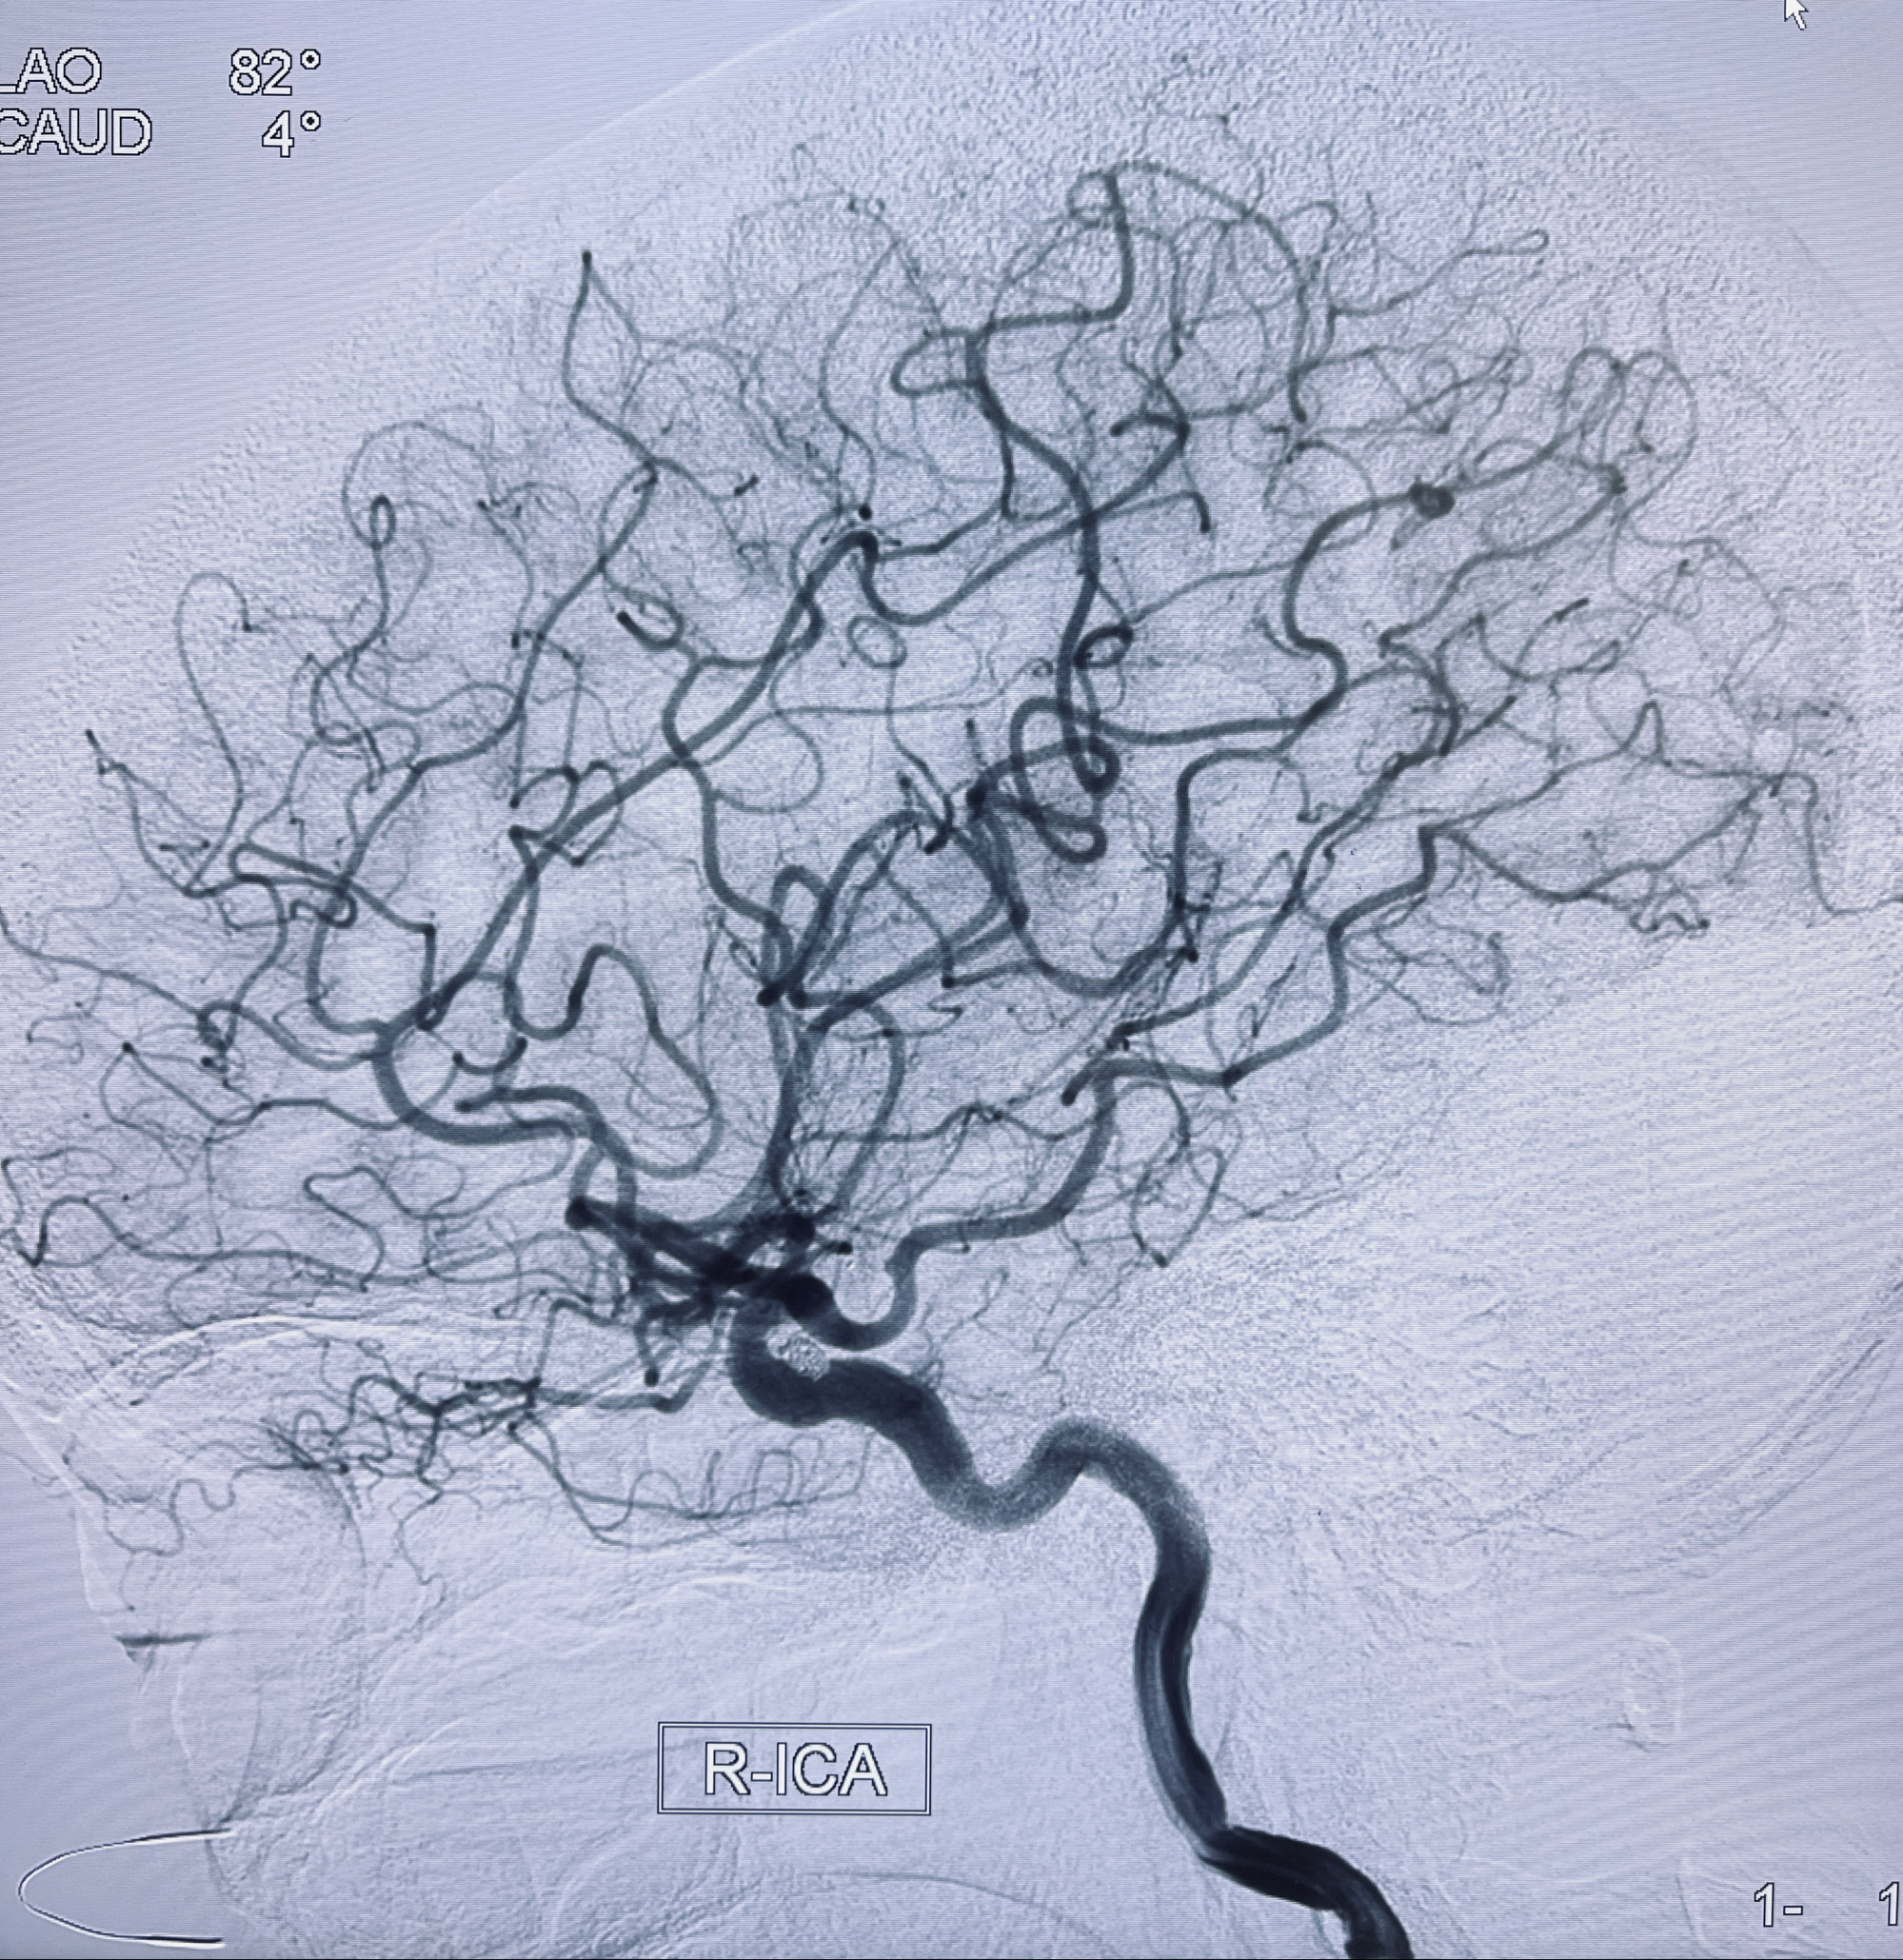

2022-09-29复查DSA